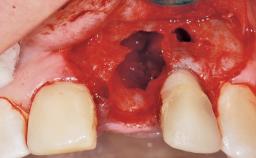

A 33-year-old female patient presented with an upper left central incisor that required extraction after a failed endodontic therapy. The tooth had been traumatized when the patient was a teenager and had undergone several endodontic treatments, including two apicectomy procedures. The patient was in good health and did not smoke. Clinical examination showed that the patient had a high lip line. In full smile, the gingival margins of the upper teeth were visible to the first molars. The gingival margins of central incisors 11 and 21 were only just showing. Examination of tooth 21 confirmed that the tooth was mobile and had hypererupted by 1 mm.

Placement Protocol Immediate implant placement

Socket Integrity Damage to one or more bone walls

Bone Volume Damage to one or more socket walls

Bone Augmentation Horizontal|Simultaneous

Augmentation Materials Xenogenous|Membrane